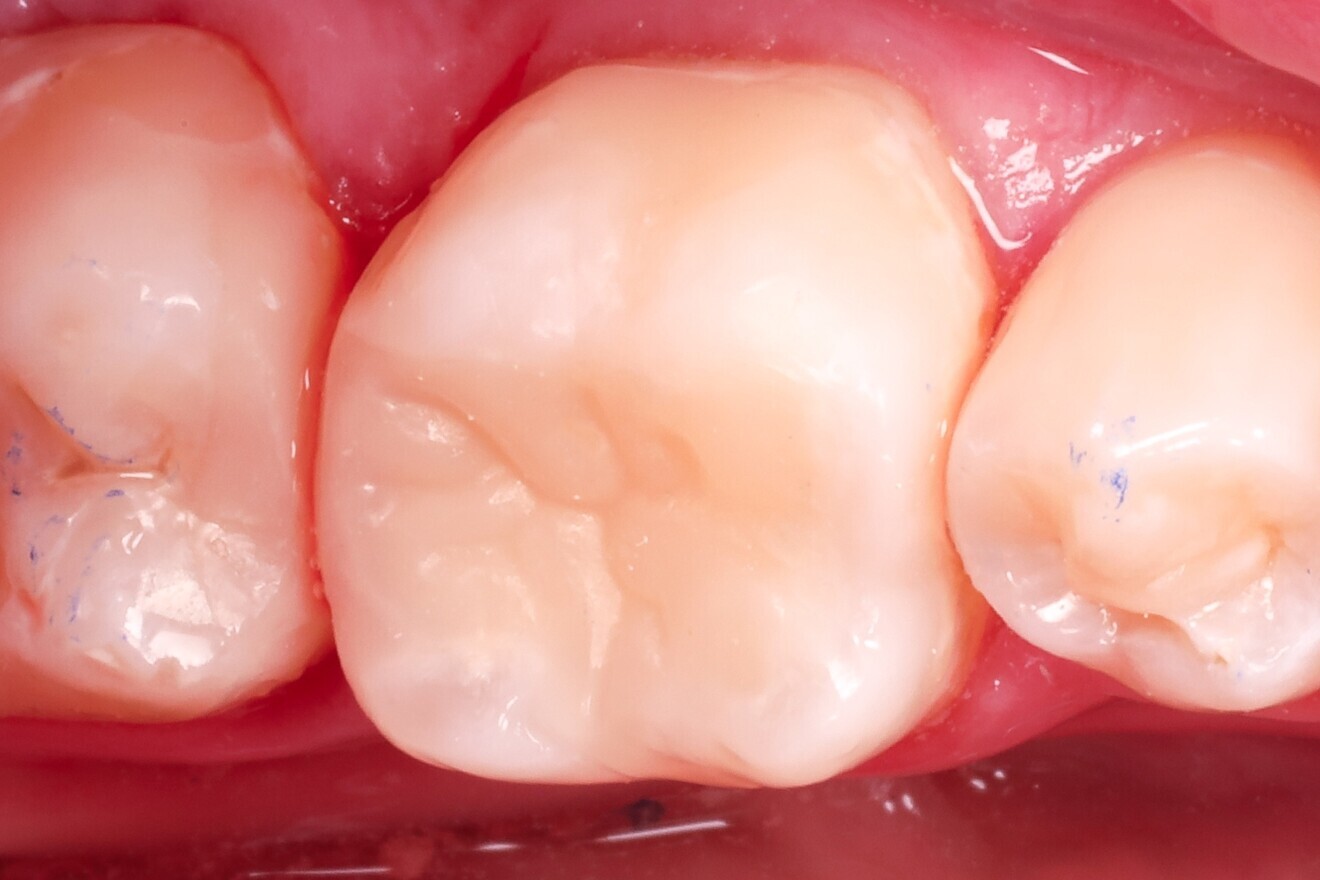

Fig. 1: Pre-op view of the mandibular first molar with existing composite restorations. (All images: Dr Péter Farkas)

Treatment focused on a mandibular first molar with existing Class I and V composite restorations (Fig. 1). The tooth was asymptomatic, and cold testing revealed a normal response. A distal carious lesion, which was not clinically visible, was first suspected during routine screening and its extent clearly identified on the panoramic radiograph (Fig. 2).